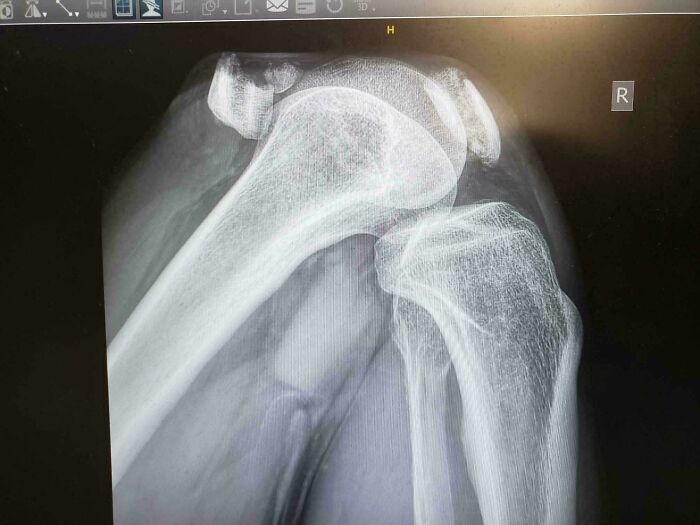

Broken Kneecap

Bro slipped and knee-dropped to the floor. After getting his knee bolted back together, a staph infection almost ended him. He's had to have three surgeries for this already. He briefly thought he was going to need a bone graft too, but thankfully it turned out not. Don't underestimate those slippery floors, folks.